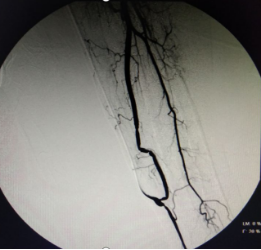

孙某某 男 69岁,尿毒症,静脉压力高达260mmhg,左上臂静脉曲张像“蚯蚓”一样,左上臂及右颈部可见膨大静脉瘤形成,检查提示左无名静脉全段闭塞。

血管“下游”堵起了,血液就从脑壳皮小血管流向对侧颈部静脉血管再汇入心脏,导致病人血管“鼓包”、头痛,睡不好觉。要想解决这个问题,首选方案是开通血管,也就是说哪里的路堵了修通哪里的路。这个病人的血管堵得很长,堵塞部位迂曲位于胸腔并靠近心脏,导丝软头配合导管无法“捅过”堵塞部位。

经过讨论,为该患者采取了DSA下使用导丝硬头配合导管锐性开通左无名静脉方案,安岳县人民医院是四川省第一个开展这一技术的县级医院。锐性开通血管风险高,面临“捅穿”血管大出血、损伤心肺临近器官风险。血液净化中心医生精心操作,成功用导丝通过闭塞部位后再使用球囊扩张导管扩张左无名静脉。

患者术后无严重并发症,术后使用原动静脉内瘘正常透析,患者眼睑浮肿、左上臂静脉曲张及静脉瘤、右颈部膨大静脉瘤消退,左上肢胀痛、头痛症状治愈,睡眠改善,生活质量明显提高。

血液净化中心医生DSA下行血管造影+开通左、右无名静脉的手术过程